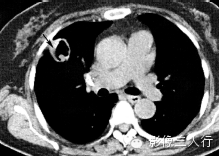

| 肺脓肿(图1) | 肺结核空洞(图2) | 癌性空洞(图3) | |

| 空洞形态 | 洞壁厚、模糊,内壁较光滑,内多见液平面 | 洞壁薄、内壁较光整,周围常有卫星灶 | 洞壁厚,多呈偏心性增厚,内壁常呈结节状 |

(B)平扫纵隔窗